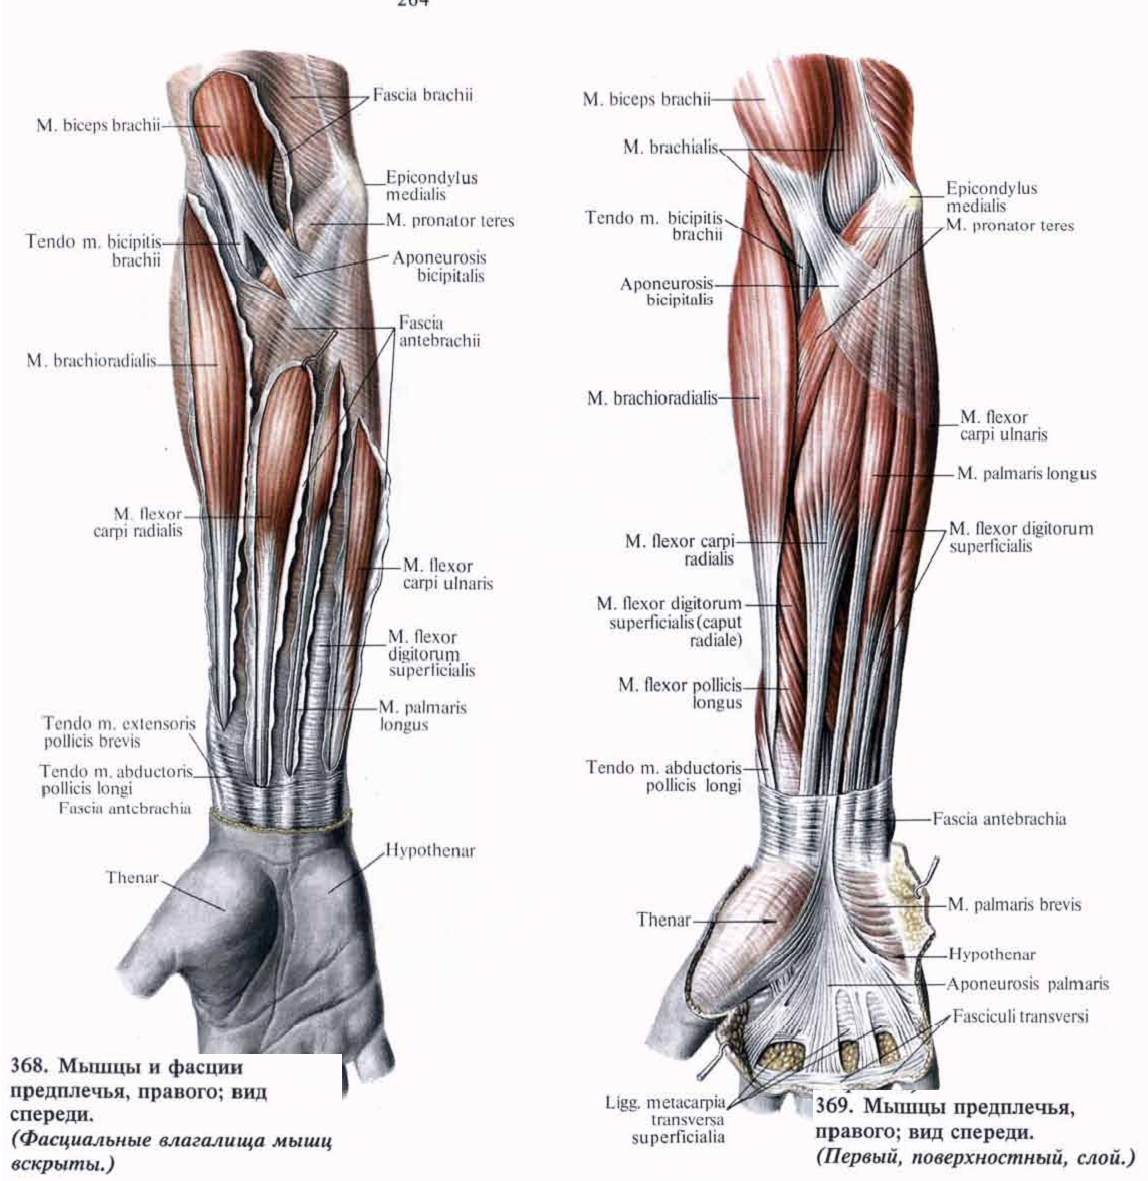

Анатомия мышцы Palmaris Longus